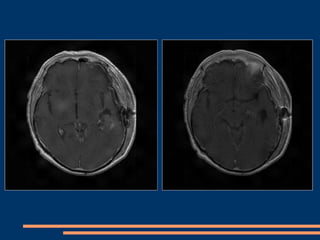

IRM post-opératoire à 3 mois

IRM post-opératoire  3 mois